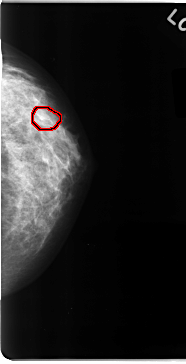

C_0090_1.RIGHT_MLO

FILE: C_0090_1.LEFT_MLO.OVERLAY

TOTAL_ABNORMALITIES 1

ABNORMALITY 1

LESION_TYPE CALCIFICATION TYPE PLEOMORPHIC DISTRIBUTION CLUSTERED

ASSESSMENT 4

SUBTLETY 4

PATHOLOGY MALIGNANT

TOTAL_OUTLINES 1

BOUNDARY

FILE: C_0090_1.LEFT_CC.OVERLAY